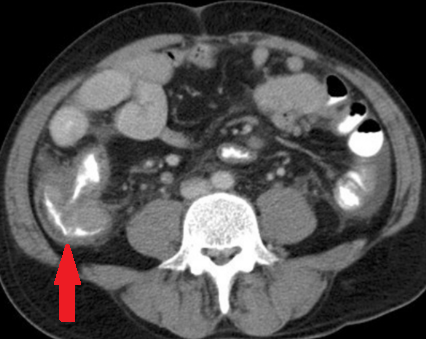

CT κοιλίας. Κόκκινο βέλος — Τυφλίτιδα. Σημαντική πάχυνση τοιχώματος τυφλού (Ευγενική παραχώρηση Dr. V. Penopoulos)